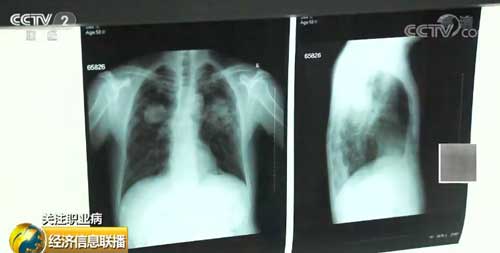

塵肺病又叫矽肺病,是指由于在職業(yè)活動(dòng)中長期吸入生產(chǎn)性粉塵并在肺內(nèi)潴留而引起的以肺組織彌漫性纖維化為主的全身性疾病。患病后,肺組織硬化、石化,導(dǎo)致呼吸極為困難,行動(dòng)艱難,喪失勞動(dòng)力。目前,塵肺病已成為中國職業(yè)病最嚴(yán)重的的病種。

數(shù)據(jù)顯示,截至2018年底,我國累計(jì)報(bào)告職業(yè)病97.5萬例,其中,職業(yè)性塵肺病87.3萬例,約占報(bào)告職業(yè)病病例總數(shù)的90%。業(yè)內(nèi)專家指出,在塵肺病的患病人群中,農(nóng)民占比高達(dá)90%。